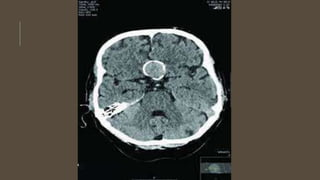

INVESTIGATIONS

• CT scan

• CT angiogram

• MRI and MRA

• DSA